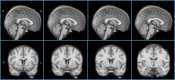

Methods: 99 PD participants and 47 control participants completed gait assessments via an instrumented walkway during 2 minutes of continuous walking, at baseline and for up to 3 years, from which 16 spatiotemporal characteristics were derived. Sub-regional cholinergic basal forebrain volumes were measured at baseline via MRI and a regional map derived from post-mortem histology. Univariate analyses evaluated cross-sectional associations between sub-regional volumes and gait. Linear mixed-effects models assessed whether volumes predicted longitudinal gait changes.

Results: There were no cross-sectional, age-independent relationships between sub-regional volumes and gait. However, nucleus basalis of Meynert volumes predicted longitudinal gait changes unique to PD. Specifically, smaller nucleus basalis of Meynert volume predicted increasing step time variability (P = 0.019) and shortening swing time (P = 0.015); smaller posterior nucleus portions predicted shortening step length (P = 0.007) and increasing step time variability (P = 0.041).